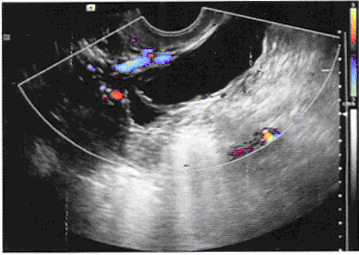

女,27岁,下腹部疼痛数月。体检:右侧附件区增厚、增大,B超检查如图所示,最可能的诊断为()。

[单选题]女,27岁,下腹部疼痛数月,体检:右侧附件区增厚、增大,B超检查如图所示,最可能的诊断为()A . 右侧卵巢囊肿B . 右侧输尿管扩张C . 右侧输卵管积液D . 盆腔积液E . 以上都不是